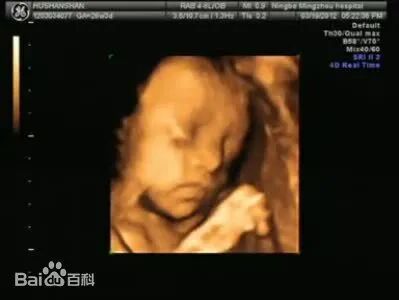

四维B超相当于在三维B超的基础上,再增加了时序维度(即第四个维度),也就是显示组织或胎儿的运动状态

例如在产前检查时,通过四维B超可以观察胎儿的曲动姿态,甚至能够观察到胎儿面部表情和手脚的动作,更加全面地了解胎儿的健康状况。

不同维度的B超技术在成像上有不同的优势,根据需要进行技术选择。

二维B超是最常用的技术,三维B超和四维B超在特定领域如产科、心脏病、肿瘤检查等方面有更广泛的应用。